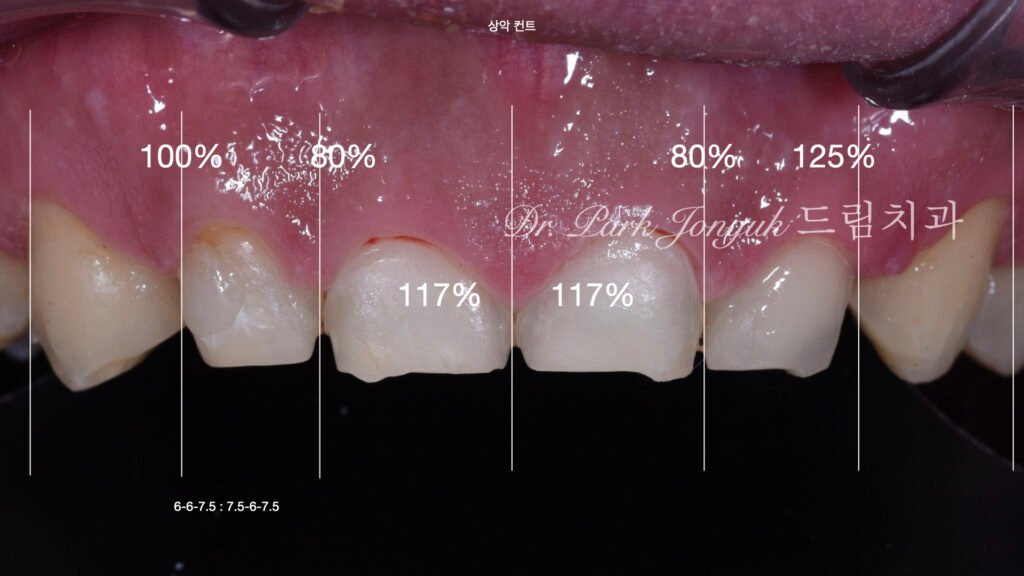

3. 정밀 진단 단계: Prescription & Inspection (사진 2, 3)

3.1 왁스업(Wax-up)을 통한 볼륨 재설계

[사진 2, 3 참조] 무삭제 방식은 삭제를 하지 않는 대신, 보철물이 얹어졌을 때의 부피감을 완벽하게 제어해야 합니다.

- 디지털 분석: 환자의 안면 구조와 스캔 데이터를 결합하여 삭제 없이도 입술 돌출감이 없는 최적의 두께를 산출합니다.

- 왁스업 결과물: 이를 실물 모형화하여 저작 시 간섭 여부와 심미적 만족도를 사전에 철저히 검증합니다.